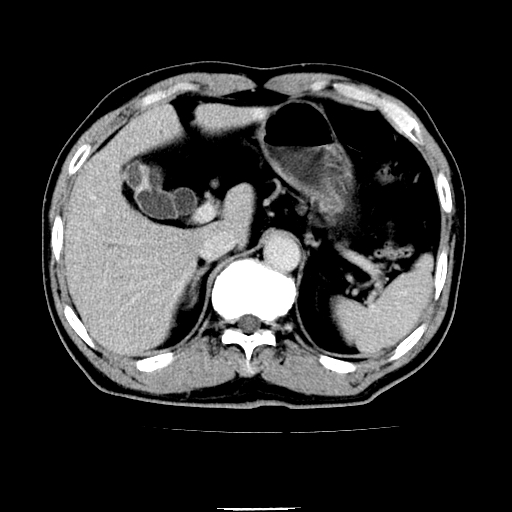

以下是引用chenqiong在2010-3-25 20:56:00的发言:[br]1、胆囊炎,胆囊息肉[br]2、肝内胆管及胆总管扩张,胆总管下端结石[br]3、十二指肠乳头旁憩室

以下是引用zxl51642在2010-3-26 10:47:00的发言:[br]胆囊炎,胆囊息肉,胆总管扩张,但未看到明显肿块,肝内胆管扩张不像恶性,炎性狭窄或阴性结石可能吧,建议mrcp,右肾小囊肿